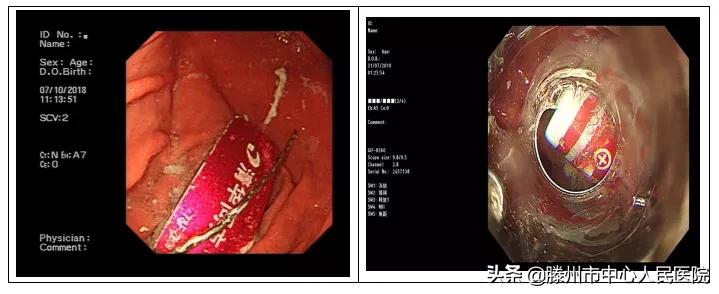

U盘和电池